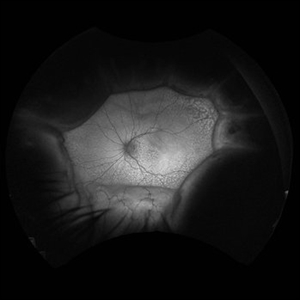

66 year old male presented with a 4 month vision of painless decreased vision in the left eye. Clinical findings consistent with idiopathic uveal effusion syndrome. Fundus photography shows 360 degree choroidal elevation with dependent inferior subretinal fluid.

Photographer: Dr. Angela Rico, Retina Specialists of Tampa